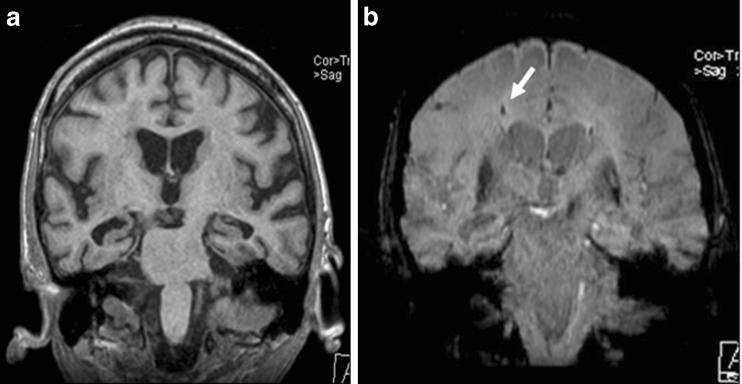

Susceptibility-weighted imaging (SWI) is a relatively new magnetic resonance (MR) technique that exploits the magnetic susceptibility differences of various tissues, such as blood, iron and calcification, as a new source of contrast enhancement. This pictorial review is aimed at illustrating and discussing its main clinical applications. METHODS: SWI is based on high-resolution, three-dimensional (3D), fully velocity-compensated gradient-echo sequences using both magnitude and phase images. A phase mask obtained from the MR phase images is multiplied with magnitude images in order to increase the visualisation of the smaller veins and other sources of susceptibility effects, which are displayed at best after post-processing of the 3D dataset with the minimal intensity projection (minIP) algorithm. RESULTS: SWI is very useful in detecting cerebral microbleeds in ageing and occult low-flow vascular malformations, in characterising brain tumours and degenerative diseases of the brain, and in recognizing calcifications in various pathological conditions. The phase images are especially useful in differentiating between paramagnetic susceptibility effects of blood and diamagnetic effects of calcium. SWI can also be used to evaluate changes in iron content in different neurodegenerative disorders. CONCLUSION: SWI is useful in differentiating and characterising diverse brain disorders.